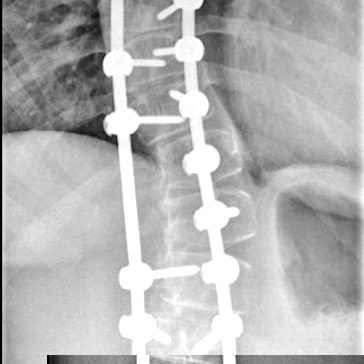

«Сколиоз – это ортопедическое заболевание, которое характеризуется сложной деформацией одновременно в нескольких плоскостях позвоночного столба и грудной клетки. Сопровождается нарушением функции органов и систем организма, является причиной тяжелых физических и психологических трудностей у детей. Обычно бывает достаточно комплексного консервативного лечения: это лечебная гимнастика, массаж, корсеты и другие методы. Редко, при работе с особенно тяжелыми случаями, требуется хирургическое вмешательство. В нашей больнице такую операцию проводили впервые, она заняла около десяти часов, потребовалась слаженная работа высококвалифицированных специалистов разного профиля – анестезиологов, нейрофизиологов, трансфузиологов, нейрохирургов, травматологов-ортопедов. В ходе хирургического вмешательства применили современный метод коррекции сколиотической деформации. Вдоль позвоночника на разных уровнях установили транспедикулярные винты. Затем на них слева и справа наложили специальные стержни, предварительно изогнутые с учетом коррекции деформации позвоночника и физиологических изгибов, они были закреплены гайками. Это конструкция позволила зафиксировать нормальное положение позвоночника и исправить искривление», — рассказал Исмаил Османов.

Благодаря слаженной и профессиональной работе врачам удалось выполнить сложную операцию, избавить молодую пациентку от постоянной хронической боли, вернуть ей подвижность, возможность вести активный, здоровый образ жизни. В настоящее время она идет на поправку и проходит мероприятия по реабилитации.